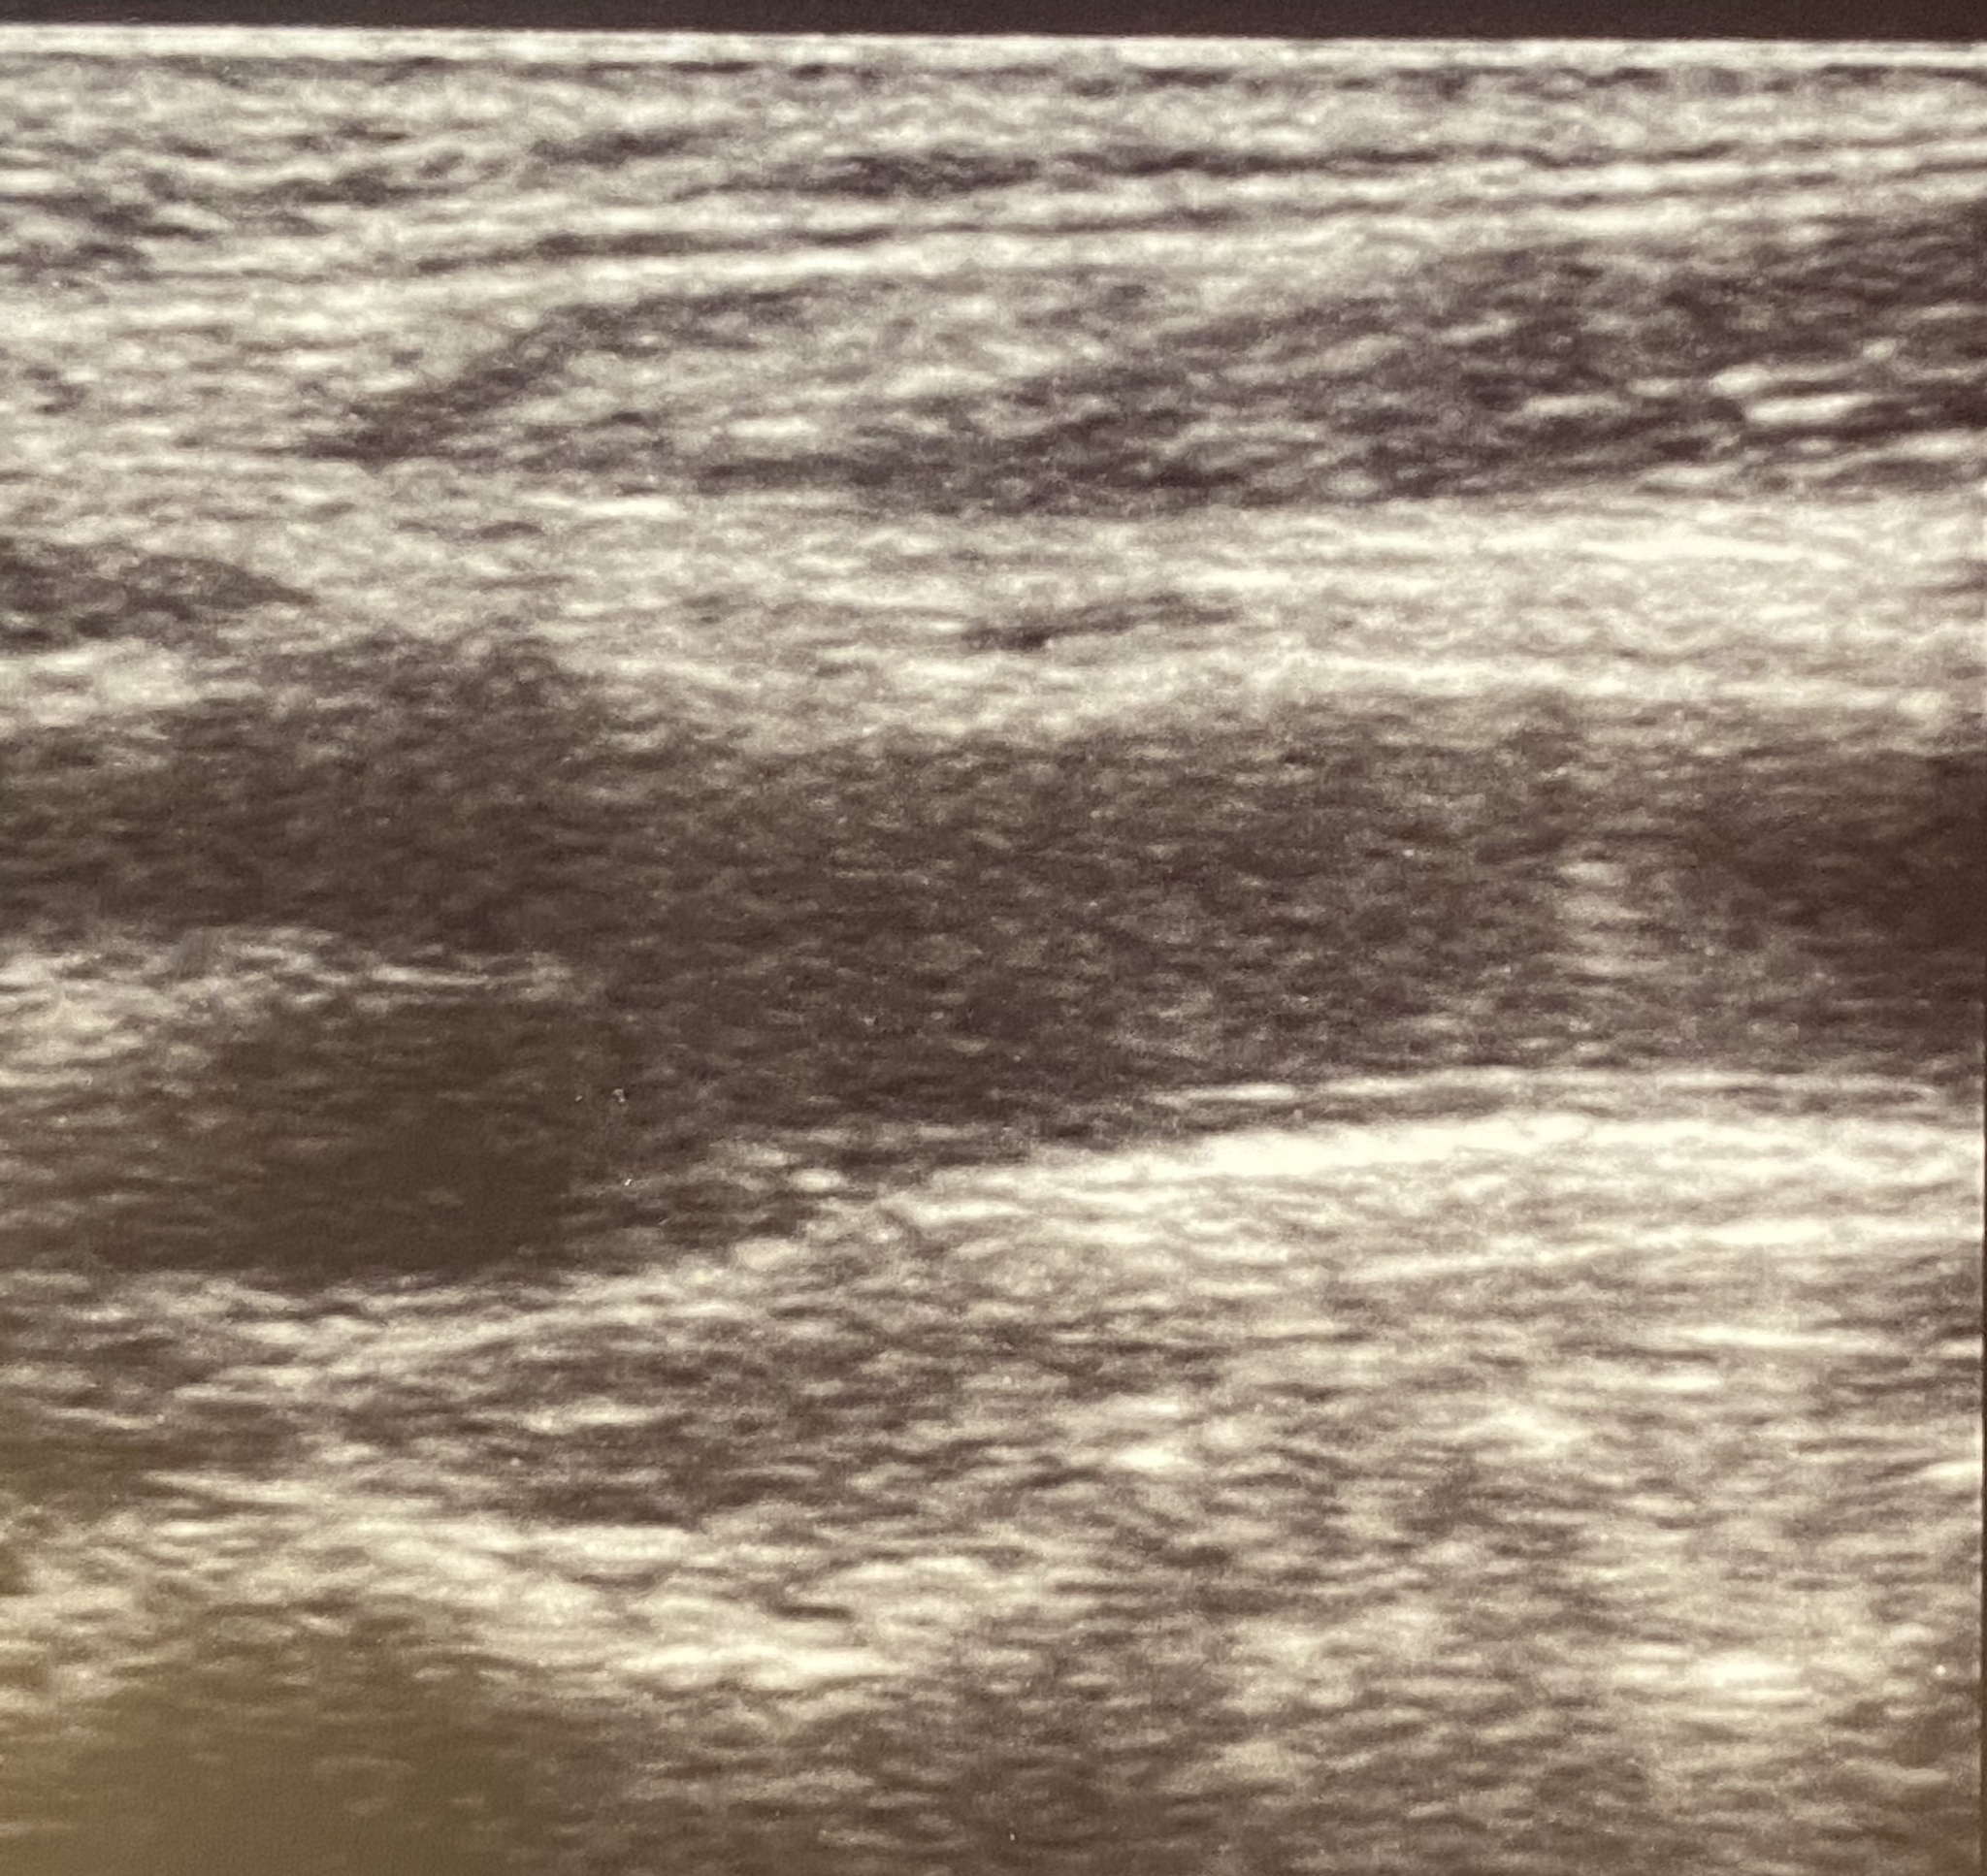

Right Internal Carotid Artery Plaque and Luminal Stenosis Detected During Admission Ultrasound

During the routine cervical artery ultrasound examination upon admission, we detected the presence of plaque in the patient's right internal carotid artery, resulting in luminal stenosis. Additionally, we observed suspected hypoechoic material at the distal end of the plaque.